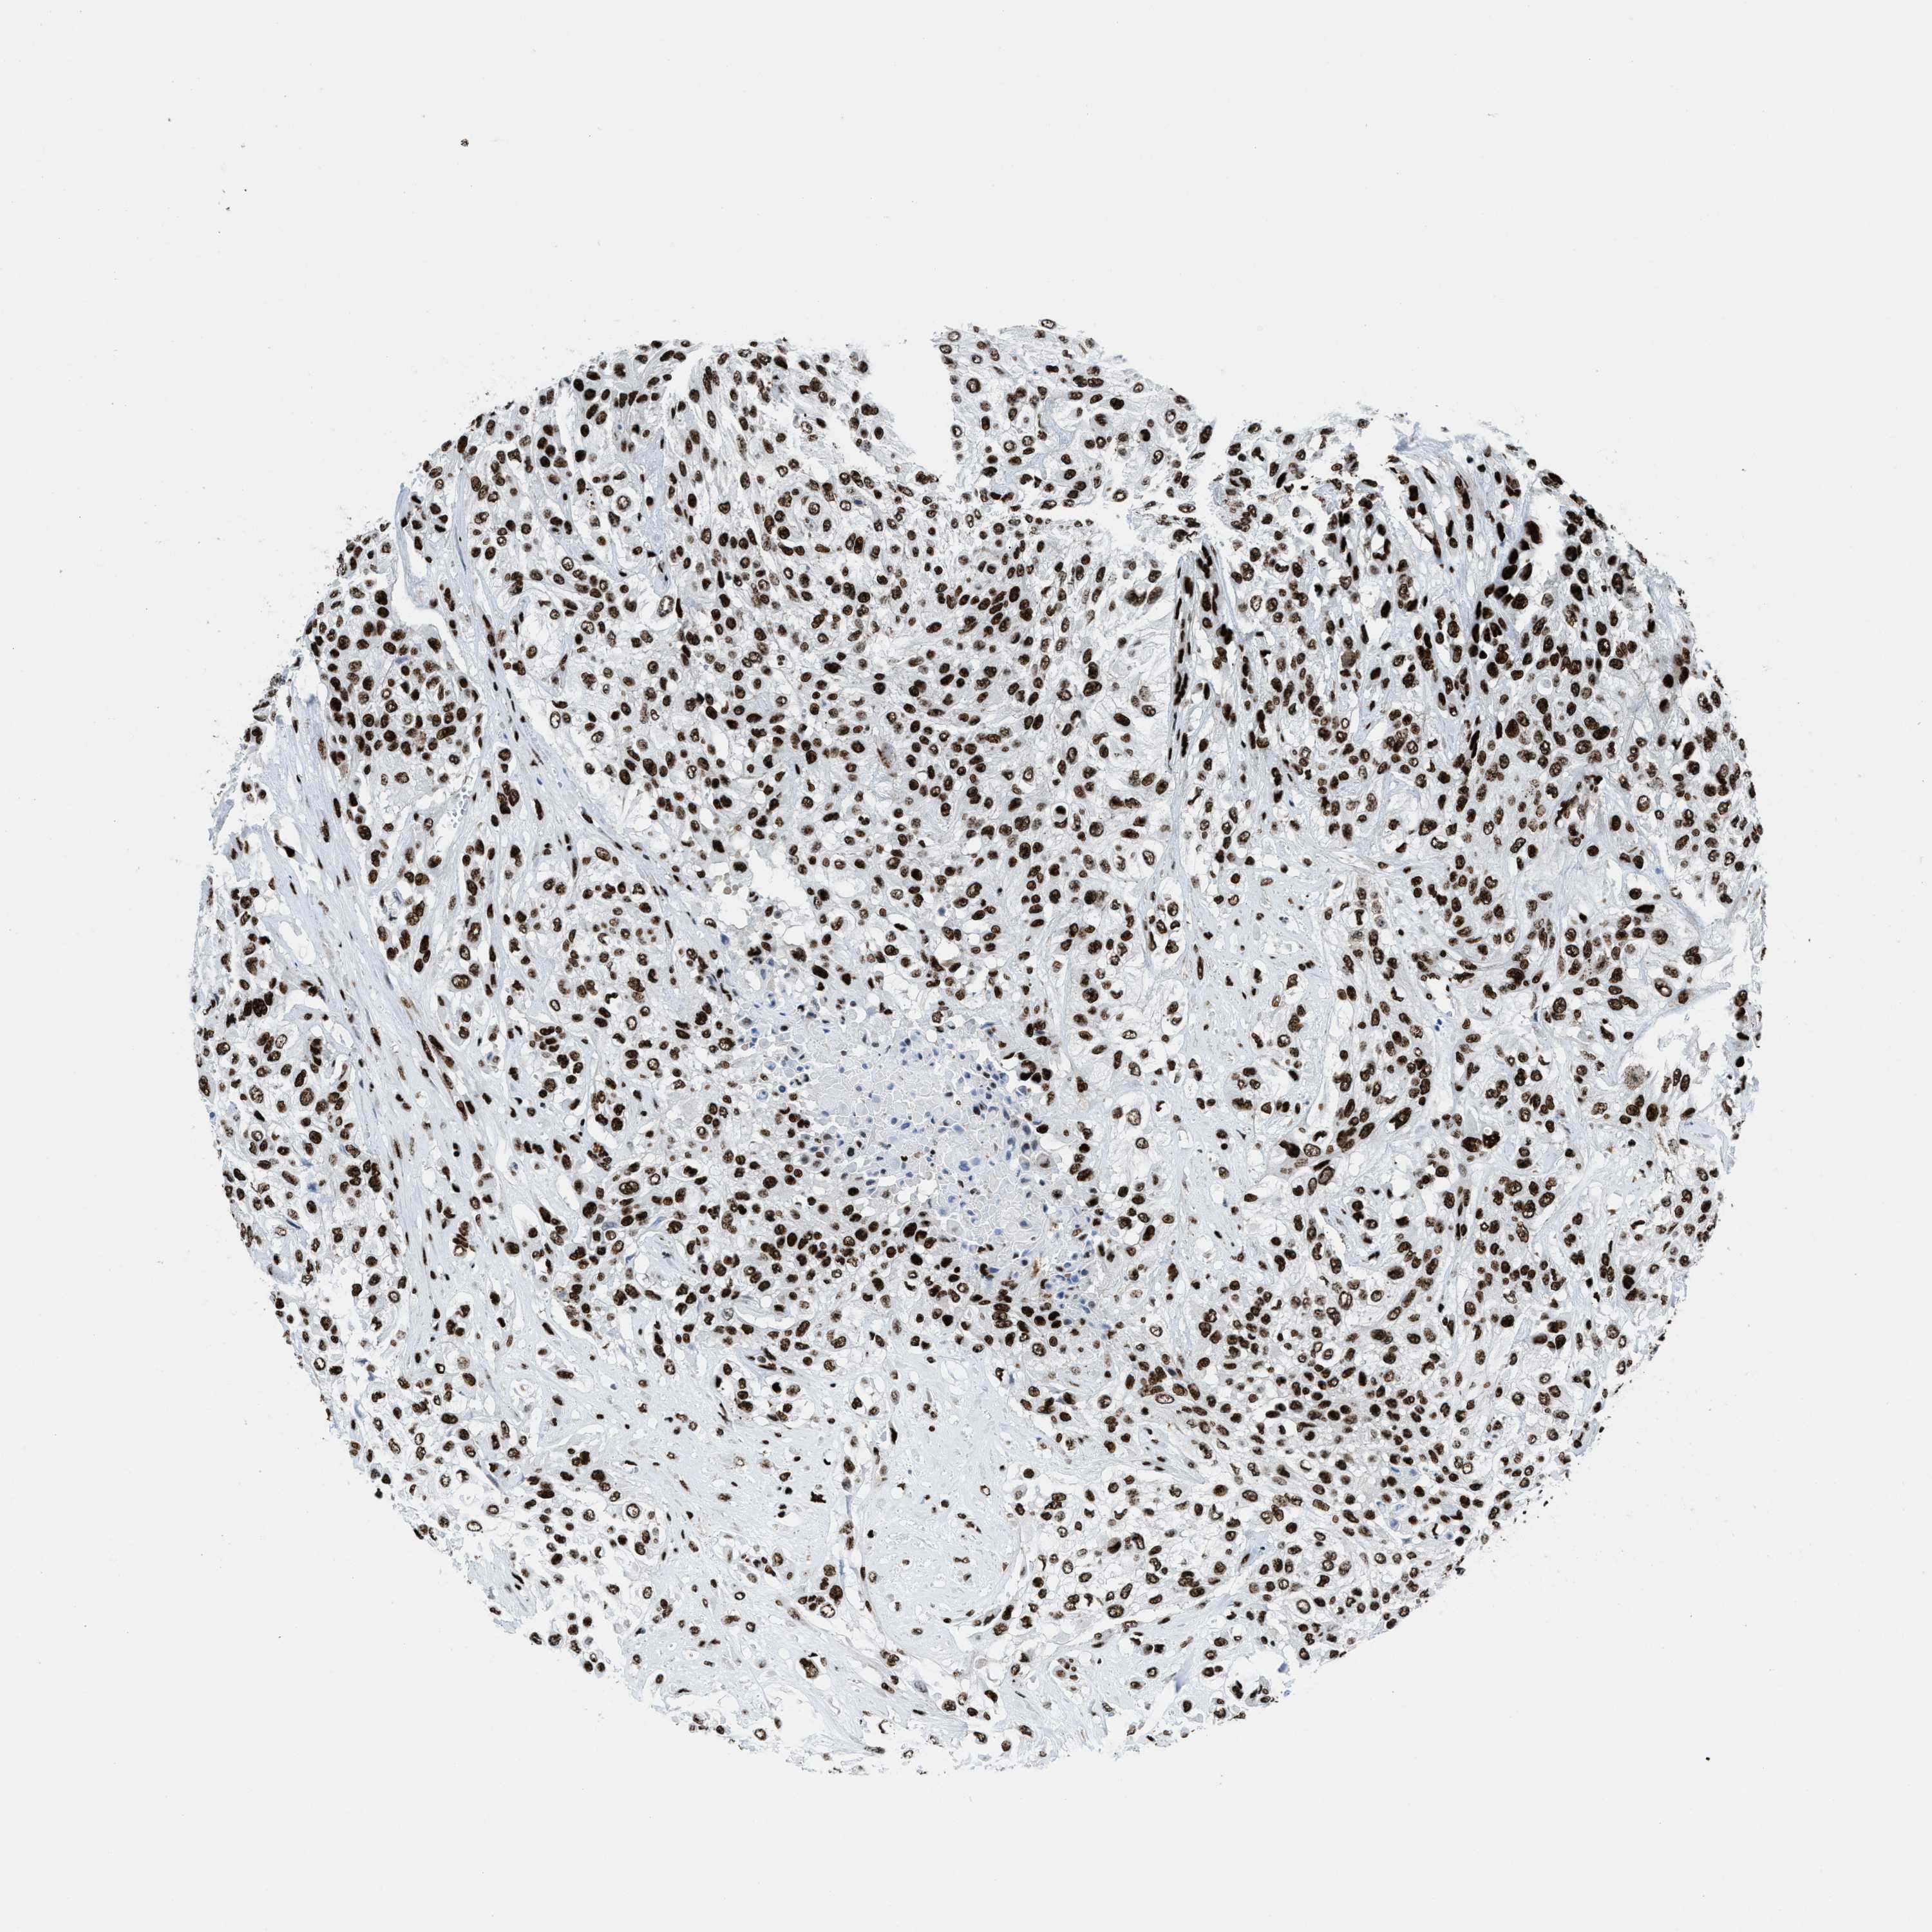

UROTHELIAL CANCER - Protein expressioni

A mouse-over function shows sample information and annotation data. Click on an image to view it in a full screen mode. Samples can be filtered based on level of antibody staining by selecting one or several of the following categories: high, medium, low and not detected. The assay and annotation is described here.

Note that samples used for immunohistochemistry by the Human Protein Atlas do not correspond to samples in the TCGA dataset.

Antibody stainingi

Antibody staining in the annotated cell types in the current human tissue is reported as not detected, low, medium, or high, based on conventional immunohistochemistry profiling in selected tissues. This score is based on the combination of the staining intensity and fraction of stained cells.

Each image is clickable and will lead to virtual microscopy that enables deeper exploration of all samples and also displays staining intensity scores, fraction scores and subcellular localization as well as patient and tissue information for each sample.

Antibody HPA054094

Antibody HPA054559

Antibody CAB022069

Staining

High

Medium

Low

Not detected

Intensity

Strong

Moderate

Weak

Negative

Quantity

>75%

75%-25%

<25%

None

Location

Nuclear

Cytoplasmic/membranous

Cytoplasmic/membranous,nuclear

Urothelial carcinoma, High grade

Urothelial carcinoma, NOS

Urothelial carcinoma, Low grade